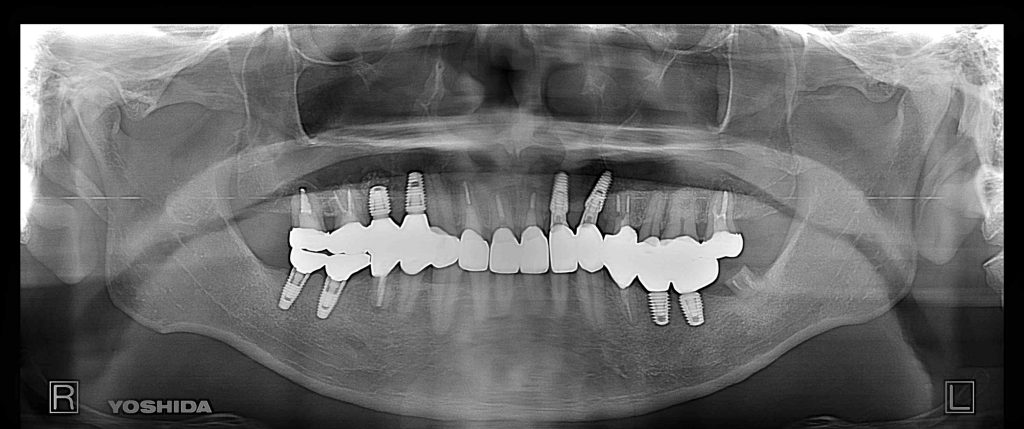

症例3 60代 男性 主訴 奥歯で噛みたい

治療前

治療後

奥歯で噛めない為、インプラントを希望され来院。

臼歯部の咀嚼回復を目的とし、口腔内全体でインプラントを5本埋入。

左右大臼歯部は、残存骨が1~2㎜程度で骨高が不足している為、ソケットリフト(上顎洞洞底膜挙上術)を行い、インプラントを埋入。

約6ヶ月の治療期間を経て、全てジルコニアを装着し終了。

リスクとしては外科的侵襲がある。デメリットは、保険外診療の為、経済的負担がある。

費用 302万(税込)(オペ・仮歯・最終補綴物まで含む)